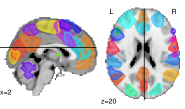

In a connectome analysis [31, 26], each subject is described by a GGM measuring functional connectivity between a set of regions. We build a connectome from brain regions of interest based on a multi-subject atlas222https://team.inria.fr/parietal/research/spatial_patterns/spatial-patterns-in-resting-state/ of 39 functional regions derived from resting-state fMRI [32] (see. Fig. 5).

We now analyse the reproducibility of the results by repeatedly sampling 100 subsets of the data (with the same proportions and ), obtaining the matrix of test statistics, selecting edges that fall below the significance level. Figure 3 shows how often edges are selected multiple times across subsamples. We report results with a threshold on uncorrected p-values as the lasso procedure selects no edges with multiple comparison correction (supplementary materials give FDR-corrected results for the de-biased fused multi-task lasso selection). Figure 5 shows a connectome of the edges frequently selected by the de-biased fused multi-task lasso (with FDR correction).